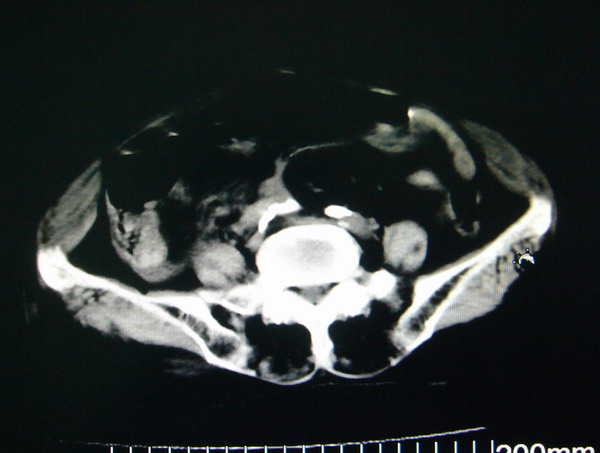

女:83y,转移性右下腹痛2小时,白细胞计数增高。

1.右侧肾盂扩大,肾盏无扩张,考虑:先天性肾盂变异可能性大。

2.胆囊扩张,考虑:胆囊炎。

3.阑尾区域可见以结节样高密度影,结合病史,考虑:阑尾结石,阑尾炎。

右下腹肠系膜增厚,结合病史支持阑尾炎.

右侧壶腹型肾盂可能,建议输路造影或增强

1.右侧肾盂扩大,考虑先天性肾盂变异或肾盂旁囊肿。

2.胆囊扩张,考虑胆囊炎。

3.阑尾区域可见结节样高密度影,结合病史考虑:阑尾结石、阑尾炎。